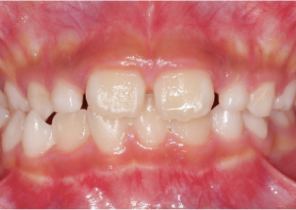

Case Report 1

10 years 0 months old, 18 stages of Invisalign Palatal Expanders

Courtesy of Dr. Sandra Khong Tai

Pre Invisalign Palatal Expander Expansion

Post Invisalign Palatal Expander Expansion

After Invisalign First treatment